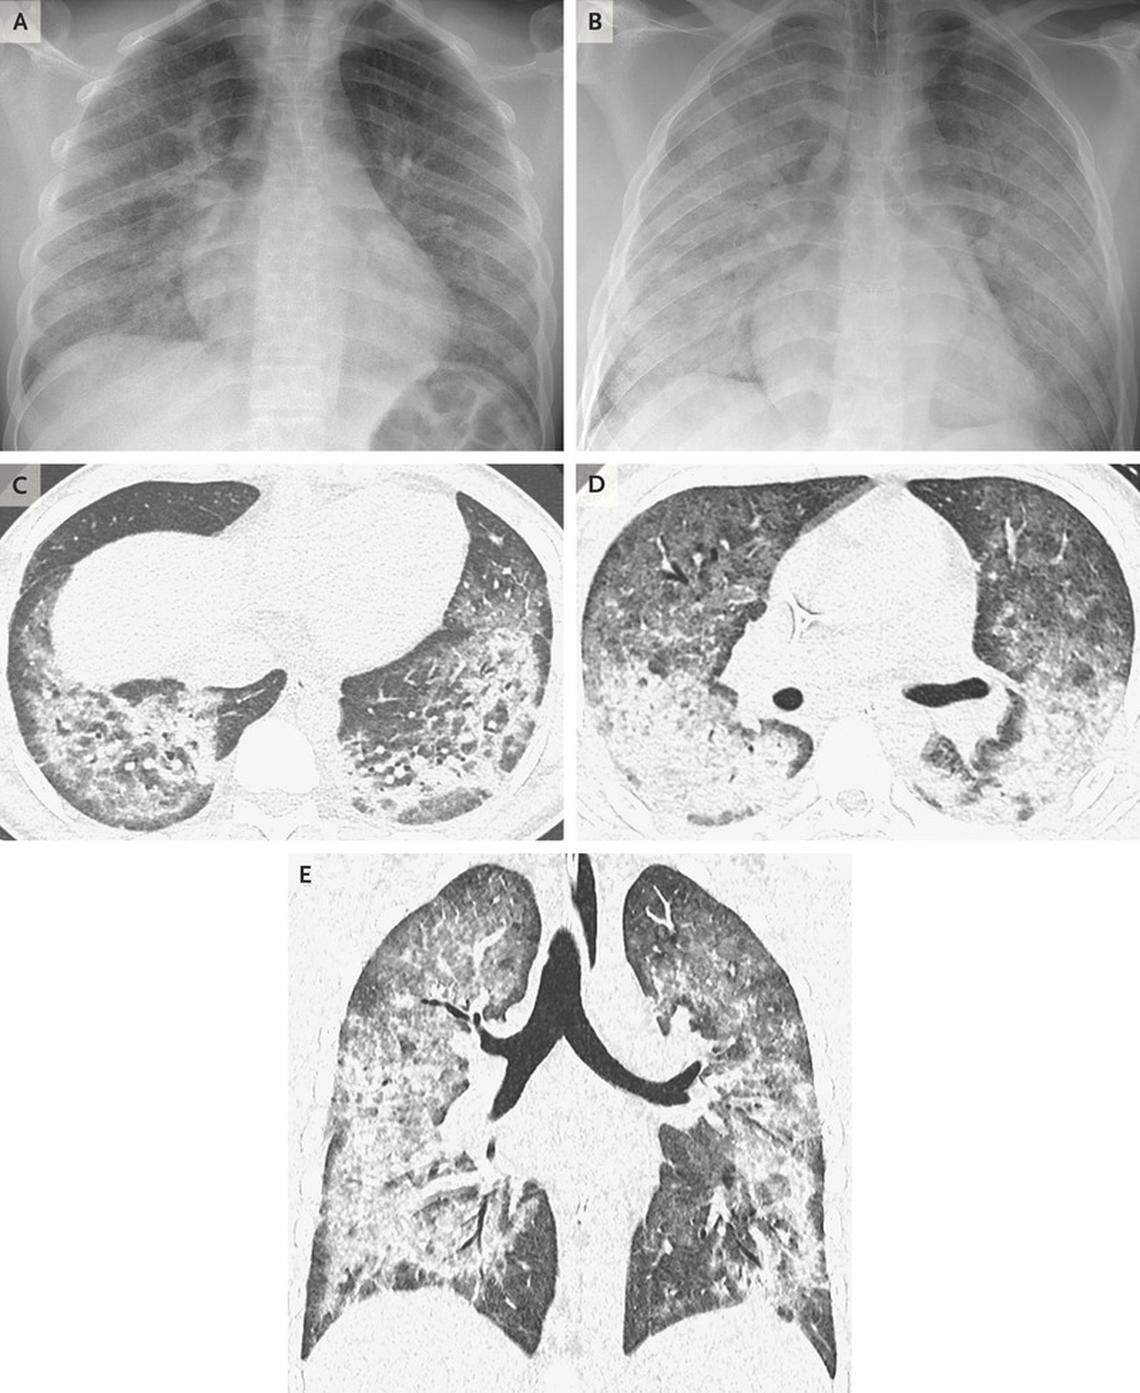

Chest radiographs and high-resolution imaging in a 17-year-old male patient with diffuse lung disease.

Chest radiographs and high-resolution imaging in a 17-year-old male patient with diffuse lung disease. New England Journal of Medicine